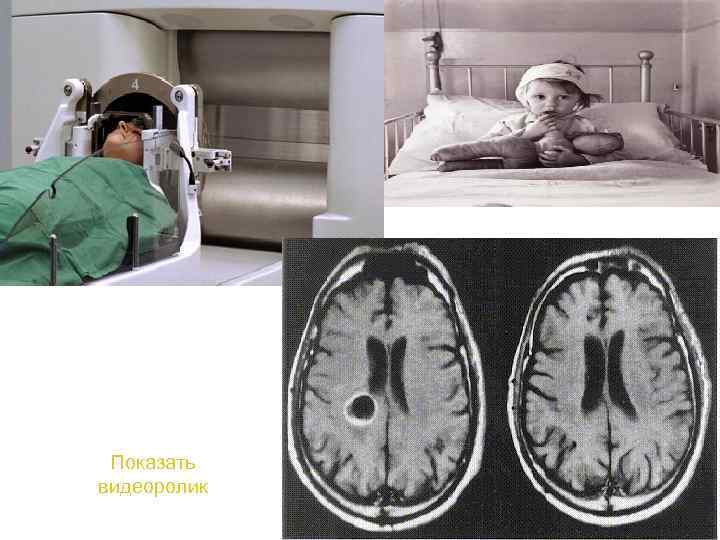

Существует несколько типов аппаратов для стереотаксической радиохирургии: Gamma Knife, LINAC, XKnife, Synergy. S, Trilogy, Cyber. Knife, Novalis и Сyclotron. Принцип работы у всех аппаратов одинаков, а различаются они источниками энергии и методами наведения излучения на цель. Так например LINAC это линеарный акселератор, который использует в своей основе рентгеновские лучи и электромагнитные волны позволяющие достичь энегии в 46 Me. V. Во время процедуры лечения аппарат вращается вокруг пациента, обеспечивая точное излучение, фокусирующееся на опухоли. В аппарате Gamma Knife используется 201 источник радиоактивного кобальта и электромагнитные волны, с возможностью достичь максимальной энергии до 1, 25 Me. V 76

1951 год. Первый радиохирургический больной: неинвазивная деструкция глубинных структур с помощью комбинации стереотаксической рамы и рентгеновской трубки привела к 77 уменьшению выраженности болевого синдрома

Показать видеоролик 83